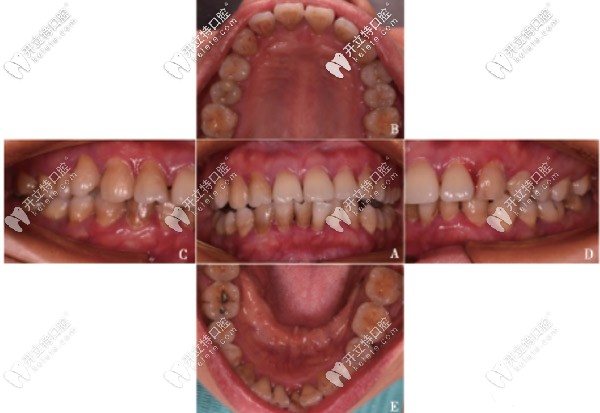

重度牙周炎案例:除了控制菌斑外還可聯(lián)合引導(dǎo)性組織再生術(shù)

顧客44歲被評估為高風(fēng)險牙周病,屬于重度牙周病范疇。經(jīng)過2年的控制菌斑聯(lián)合引導(dǎo)性組織再生術(shù),已可維持整個牙周系統(tǒng)的健康與穩(wěn)定。